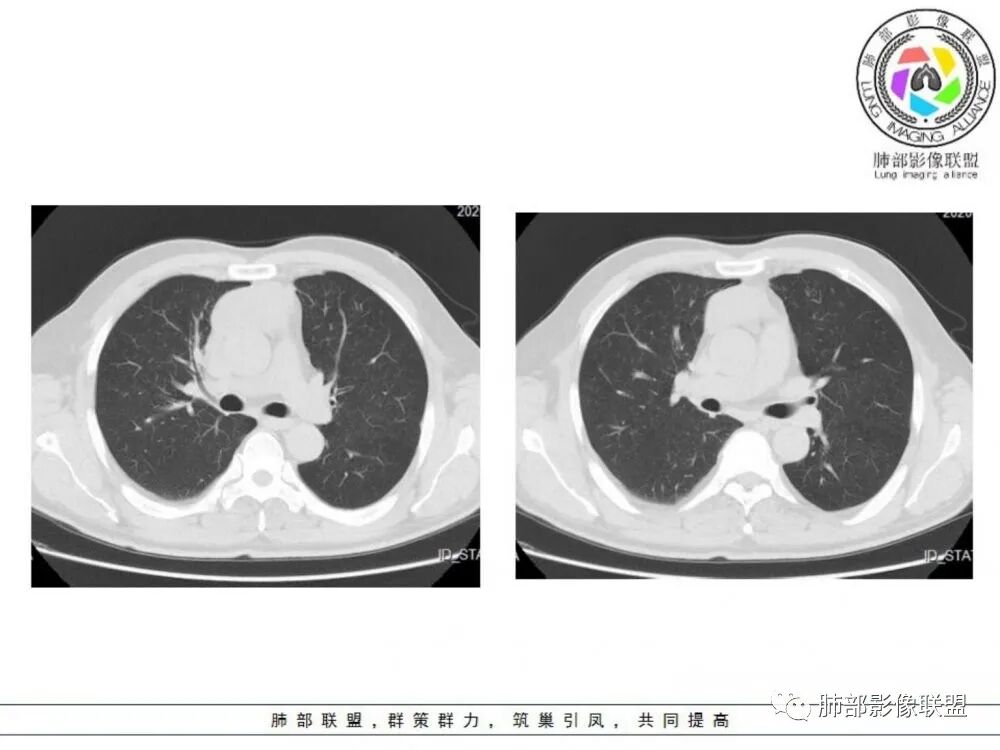

男性患者,65岁,前胸后背疼痛一个月。影像学前上纵隔分叶状的软组织肿块,肿块形态怪异,偏软,位于大血管间隙前,并有向血管后间隙发展的趋势,平扫CT值为40左右,增强扫描中心部未见强化,周围轻度的强化,约为50左右。前上纵隔的疾病谱包抬胸廓内甲状腺肿、胸腺瘤/癌、畸胎瘤、淋巴瘤。少见的心包囊肿或支气管囊肿。根据肿块的形态及强化特点,首先还是排除了胸内甲状腺肿及胸腺来源的肿物,这类的肿物强化比较明显。畸胎瘤成分比较复杂,具有软组织钙化或者脂肪类的组织,这个肿物虽然在平扫的时候好像有斑点状的钙化灶,但是总体成分还是比较单一,所以还是排除畸胎瘤的诊断。所以这样的情况是考虑:淋巴类的肿瘤,注意排除心包的囊肿或支气管来源的囊肿。

老年男性患者,前膈软组织肿块,边缘轮廓不光整,边界似乎尚清晰,内见小点状钙化灶,平扫密度欠均匀,增强后轻度强化表现,边缘有些斑片状的高强化区。综合考虑胸腺瘤或胸腺鳞癌,神经内分泌癌强化弱了一些。患者年龄较大,生殖细胞肿瘤不考虑,淋巴瘤血管包绕不够,可能性不大

老年男性,前胸后背痛一个月,前纵隔不规则肿块,分叶,向纵隔血管间隙进入,且与纵隔血管分界不清,增强边缘轻度强化,中间可见无强化区,似见点状钙化,PET为高代谢,考虑为来源于胸腺,胸腺瘤或胸腺鳞癌可能

临床,老年男性,病史一月。1 定位,骑跨大血管,大部分位于胸腺区域内,周边部分胸腺脂肪有混浑浊,起源于胸腺区的组织应该没有问题。2 定性 。恶性征像,分叶,大血管侵润,pet高代谢,左侧庄层胸膜增厚(类似脑膜瘤的脑膜尾征,良性表现?)。良性征像,病灶均匀,无明确坏死?综合恶性征像多些,考虑恶性可能大。病灶分两部分,部分层面似有明确分割,两个性质的病灶长一块,还是,一个病灶两种不同成分?一个病灶伴均匀坏死?CT值41hu,坏死好像高了点,一个病灶,相同成分,只是血管分布不同,增强是持续流入型强化。纤维类?编不下去了,岔路太多,祭出法宝按概率蒙吧:侵袭性胸腺瘤>神经纤维瘤>乏血供CD

男性患者,65岁,前胸后背疼痛一个月。胸部影像:前上纵隔分叶状的软组织肿块,形态不规则,包绕大血管生长趋势,与周围分界不清,密度较均匀,呈多结节融合,肿块周围可见肿大淋巴结,内乳动脉旁淋巴结大,上腔受累,肿物内可见低密度区,增强扫描周围轻度强化。考虑:恶性病变,淋巴瘤?胸腺神经内分泌肿瘤?鉴别胸腺瘤

老年男性,前纵隔肿块,形态不规则,右侧内乳动脉增粗,与血管脂肪间隙模糊消失,定性恶性,周围多发小淋巴结,有斑点状钙化灶,增强中心低密度区无强化,边缘强化为主,首先考虑胸腺鳞癌,鉴别胸腺瘤。

中老年男性,前纵隔占位,基本居中,向两侧生长;边缘膨隆分叶,部分边界不清,增强不均匀轻中度强化,坏死区边界不清;周围多发增大淋巴结,考虑恶性。主要在胸腺癌、胸腺瘤、淋巴瘤之间鉴别。病灶偏软,有钻缝样生长,这些征象偏向于淋巴瘤。但此例老年患者,病灶内有点状钙化,缺乏结节堆砌感,倾向胸腺癌诊断。